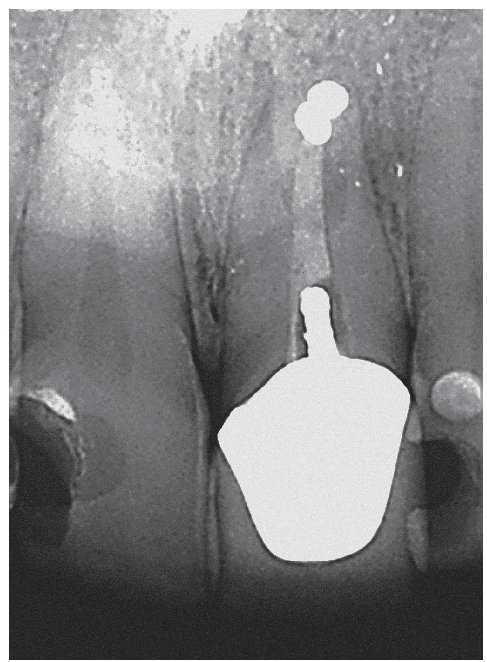

Figura 2a. La radiografía diagnóstica del diente 47 muestra una periodontitis apical postendodóntica.

Figura 2b. En sentido vestibular ya se observa un trayecto fistuloso.

Figura 2c. Situación después de la apertura cameral: la obturación existente carece de sellado marginal. No se identificó la luz del conducto radicular original. Alrededor del material de obturación se detecta tejido necrótico de aspecto negruzco, sobre todo en la zona distal donde el conducto radicular adopta una forma marcadamente ovalada. Se pasó por alto y no se preparó el istmo frecuentemente existente en los molares inferiores entre el conducto mesiovestibular y el conducto mesiolingual.

Figura 2d. Después de limpiar el suelo de la cámara pulpar salen a la luz las estructuras del sistema de conductos radiculares que se pasaron por alto en el primer tratamiento.

Figura 2e. Situación después del retratamiento de los conductos principales. Se aprecia con claridad el tejido existente en el istmo mesial.

Figura 2f. Situación después de la preparación completa del istmo mesial coronal. Se pudo palpar otro istmo en el tercio medio de la raíz mesial a través del que fluyó líquido de irrigación. Se preparó este istmo mediante instrumentos ultrasónicos.

Figura 2g. Situación después de la obturación termoplástica. Los istmos también muestran un buen sellado marginal.

Figura 2h. Radiografías de control después de la obturación: el tamaño de la luz obturada es considerablemente mayor en comparación con el tratamiento inicial. Se consiguió una obturación homogénea de los dos istmos situados en la parte coronal y apical de la raíz mesial.

Figura 2i. La radiografía de control realizada a los 12 meses mostró una curación ósea completa de la lesión apical.